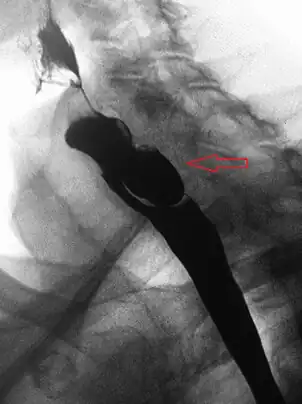

Lateral X-ray of a Zenker's diverticulum

AP X-ray of a Zenker's diverticulum